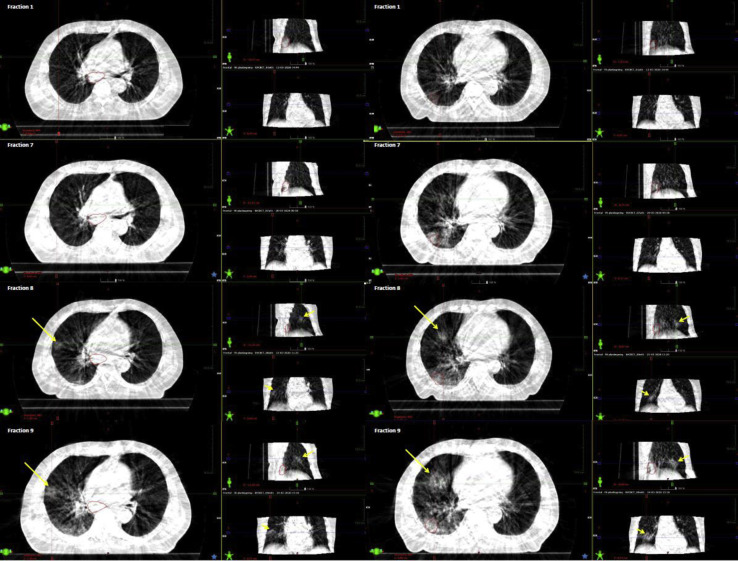

On retrospective workup, a senior radiologist assessed the daily-acquired cone beam computer tomography (CBCT). The CBCT acquired at the first treatment fraction revealed no new infiltrates in the lung tissue. Similar findings were found on the CBCT acquired at the seventh fraction. On the CBCT acquired at the eighth fraction, two ground-glass opacities (GGOs) with patchy consolidation were found, one in a subpleural location and one more centrally in the middle lobe. At ninth fraction, progression of the infiltrates in the middle lobe was observed, and one new GGO appeared in a subpleural location in the right upper lobe. These GGOs were, hence, visible on the CBCT images up to 36 hours before the patient exhibited the clinical symptoms of coronavirus disease 2019 (COVID-19) (Fig. 3 ).

Figure 3.

Daily imaging during radiotherapy: The cone beam computer tomographies taken as image guidance. Left and right panels focus on two different areas in the lungs that had changes in the lung tissue at treatment fractions 8 and 9. No changes in the lung tissue were detected on fraction 7; however, there was a 3-day interval between fraction 7 and 8 (i.e., the weekend).